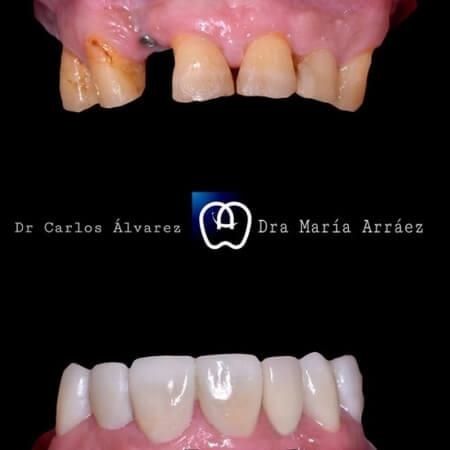

Galería de antes y después